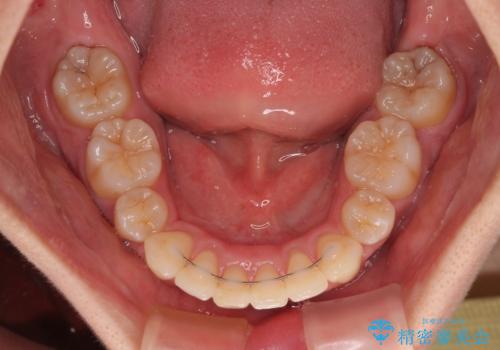

全顎的なデコボコと口元の突出感 ワイヤー装置での抜歯矯正で整った口元に

- 奥歯も含めて全体的なデコボコと前歯の突出感を気にして来院された患者様です。

上下左右第一小臼歯4本を抜歯し、ワイヤー装置にて矯正治療を行うこととしました。

想像以上に咬合力が強く、抜歯したスペースを閉じきるまでに長期間を要することとなりました。

前歯の突出感がなくなり、仕上がりには大変満足していただけました。